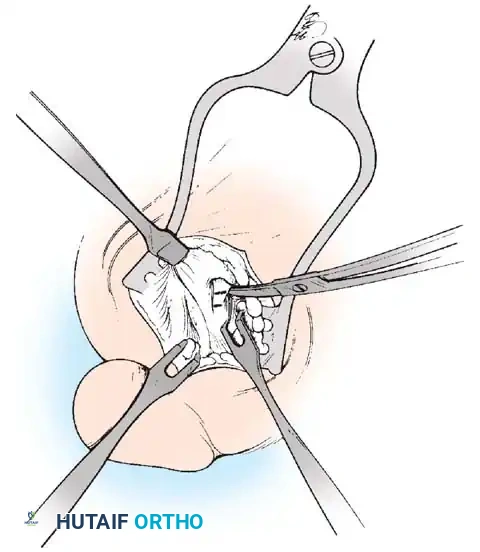

MEDIAL CAPSULAR IMBRICATION AND WOUND CLOSURE

• With an assistant holding the metatarsophalangeal joint in a congruously reduced position in the varus-valgus and fl exionextension planes, imbricate the medial capsule in the following manner (Fig. 78-22).

• Using absorbable 3-0 or interrupted sutures, place the initial suture through the plantar fl ap of the capsule at a point 4 to 5 mm medial to the proximomedial border of the medial (tibial) sesamoid and in an outside-to-inside direction.

• Turn the needle on itself, and pass it through the dorsal fl ap at the same level in an outside-to-inside direction. Immediately pass the suture back through the dorsal fl ap from inside out and fi nally through the plantar fl ap from inside out (a swedged-on needle would suffi ce, but a small, cutting needle is recommended).

• With the hallux held in the desired position, tie this suture, bringing the plantar fl ap over the dorsal fl ap and pulling the plantar-displaced abductor hallucis toward the midline of the longitudinal axis of the proximal phalanx and fi rst metatarsal.

• Allow the toe to rest unassisted to judge its resting posture and the tension on the capsular repair.

• If the fi bular sesamoid has been removed, do not imbricate the medial capsule, to avoid pulling the tibial sesamoid medial to the metatarsal head (Fig. 78-23). If a large medial eminence has persisted for many years with increased capsular reaction and redundancy, a portion of the dorsal fl ap may need to be excised before closure.

• It is imperative to avoid pulling the medial side of the tibial sesamoid medial to the articular surface of the fi rst metatarsal head; do not uncover the tibial sesamoid (Fig. 78-24).

• If the resting posture of the hallux is acceptable, close the remaining portion of the capsule with interrupted 2-0 or 3-0 absorbable sutures.

CLOSURE OF THE INVERTED-L CAPSULOTOMY

• Begin the closure proximally using 3-0 sutures on a small swedged-on needle; bending the needle to increase the curve makes passage easier in a small wound (see Fig. 78-16E).

• While an assistant applies tension distally on the free corner of the capsule, place the most proximal suture in the longitudinal limb of the capsular incision; place two or three sutures at 5-mm intervals. Do not place the corner suture.

Fig. 78-22 Modifi ed McBride procedure. Medial capsule is imbricated, with plantar fl ap over dorsal fl ap. Inset, Cross section through metatarsal head.

• Begin to close the transverse limb of the incision at the medial plantar corner.

• Hold the hallux reduced on the metatarsal head while tying all sutures.

• Unless the capsule is redundant, do not imbricate the medial capsule over the area of eminence removal. Close this portion of the transverse limb with side-to-side sutures, and place the imbricating suture in the dorsomedial corner of the capsulotomy.

• Begin this fi nal suture distally on the transverse limb of the inverted L , passing the needle from the outside in.

• Reverse the needle, and enter the capsular fl ap from the outside in on the transverse limb.

• Reverse the needle, and reenter the capsular fl ap from the inside out on the longitudinal limb of the fl ap.

• Make the fi nal pass of the needle from the inside out on the dorsal side of the longitudinal limb of the incision. Holding the joint in its reduced position, tie the suture.

• If the joint reduction is congruent, but the hallux is still in an unacceptable valgus position, metatarsal osteotomy should be considered.

• If the transverse limb of the capsular repair is too loose, allowing the hallux to slide into valgus, remove the midline medial suture in the transverse limb. While holding the hallux in the proper position, place the suture 2 to 3 mm farther away from the incision, or excise more capsule from the proximal portion. Take care in removing any extra capsule because removal of even a small portion results in a signifi cant correction of capsular laxity and may cause varus of the hallux.

• At the conclusion of the procedure, the hallux should rest on the metatarsal head in about 5 degrees of valgus and 10 degrees of extension.